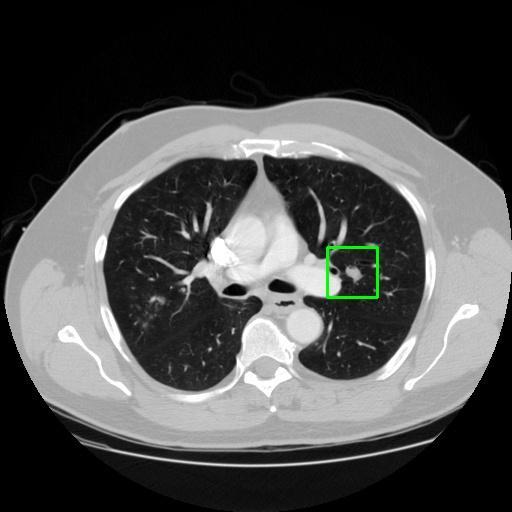

We developed an AI-based system using deep learning models for analyzing lung CT scans to detect and classify pulmonary nodules. We chose the YOLOv11 architecture for its enhanced object detection capability and adapted it specifically for medical imaging, incorporating pixel-level precision and severity classification.

Classification into three severity levels with colored bounding boxes.

Successfully built and deployed an AI model (YOLOv11) capable of detecting lung nodules in CT scans with high accuracy and real-time performance.

Designed a severity classification system that categorizes nodules into null, moderate, and severe using colored bounding boxes, assisting in rapid clinical decision-making.